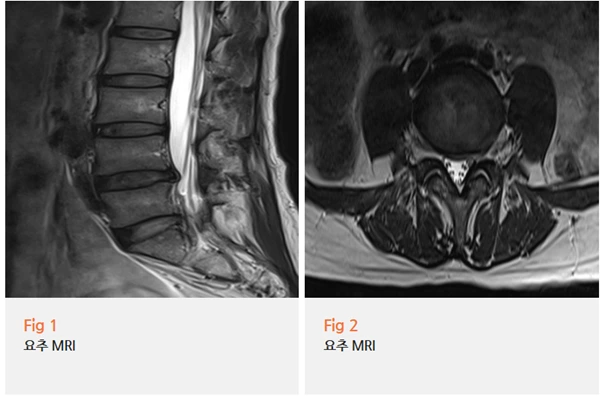

요추 MRI를 보니 요추 4번-5번, 5번-천추 1번 사이에 추간판 탈출증,

즉 허리디스크가 확인됐습니다.

디스크가 튀어나오면서 신경을 누르고 있었던 거예요.

추가로 시행한 하지 근전도 검사에서는

만성 요추 신경근병증 소견도 함께 확인됐습니다.

이 말은 신경이 눌린 지 꽤 시간이 지났다는 뜻이에요.

반면에 고관절 MRI에서는 특별한 구조적 문제가 발견되지 않았습니다.